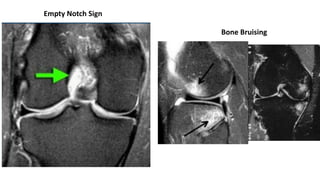

MRI

Sensitivity 97%

Specificity 100%

Empty Notch Sign

Bone Bruising